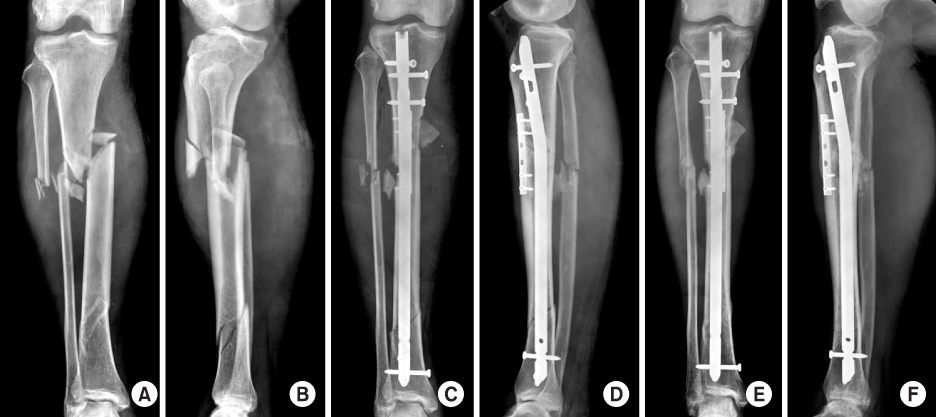

Fig. 7

(A, B) Initial radiographs show simple oblique fracture of the proximal tibia.

(C, D, E) The fracture was reduced and alignment was maintained by temporary percutaneous use of pointed reduction forceps during nailing procedures.

(F, G) Postoperative radiographs show anatomical reduction of the fracture after fixing with a locked tibial nail and adjunctive percutaneous lag screws.

Fig. 7 (A, B) Initial radiographs show simple oblique fracture of the proximal tibia. (C, D, E) The fracture was reduced and alignment was maintained by temporary percutaneous use of pointed reduction forceps during nailing procedures. (F, G) Postoperative radiographs show anatomical reduction of the fracture after fixing with a locked tibial nail and adjunctive percutaneous lag screws.